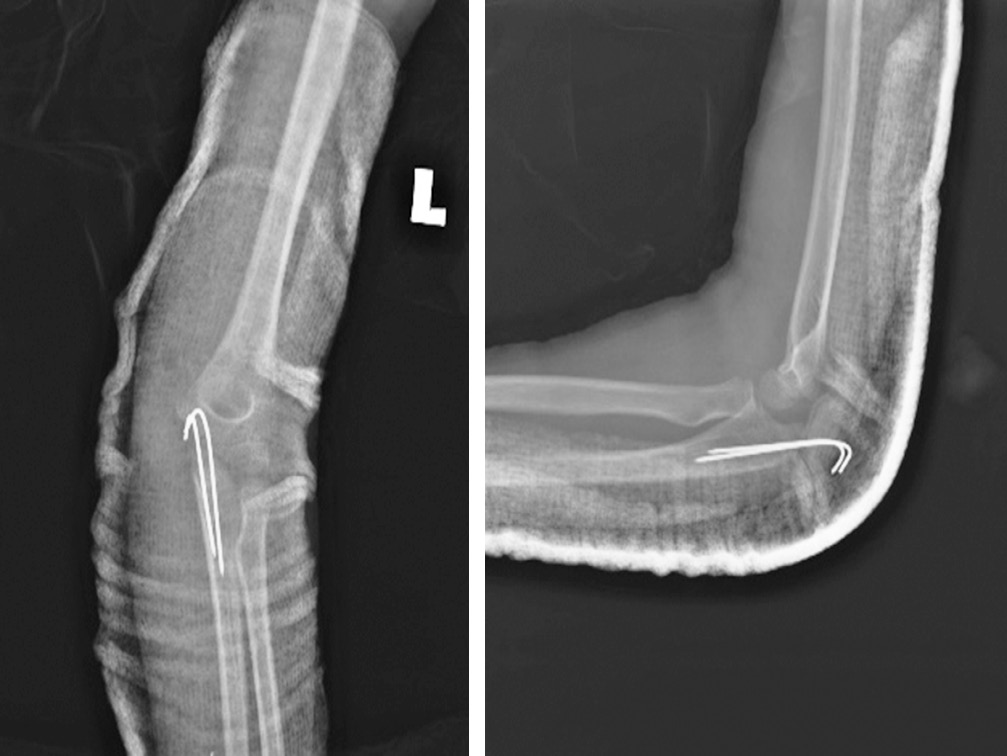

На обзорной рентгенограмме левого локтевого сустава выявлен передний вывих с переломом локтевого отростка (рис. 1). Примерно через два часа после травмы в отделении скорой помощи была предпринята попытка закрытого ручного устранения вывиха, которая оказалась неуспешной. Приблизительно через 6 ч после травмы под общей анестезией выполнено открытое устранение вывиха с чрескожной фиксацией спицей Киршнера. Для ревизии локтевого нерва и репозиции перелома выбран медиальный доступ. Интраоперационно обнаружено ущемление локтевого нерва дистальным фрагментом локтевой кости несколько дистальнее борозды медиального мыщелка. Нерв был натянут, его цвет казался слегка бледным, но целостность была не нарушена. Лучевой нерв был мобилизован проксимально и дистально до исчезновения натяжения. Перелом локтевого отростка произошел в области метафиза, при этом отломок кости был прикреплен в метаэпифизарной зоне, что соответствовало перелому II типа по Salter-Harris. Для репозиции выполнена осторожная контролируемая тракция за локоть. Перелом фиксирован двумя параллельными спицами Киршнера, репозиция головки лучевой кости была спонтанной. Полностью разорванная медиальная коллатеральная связка была восстановлена с помощью рассасывающейся нити 5/0. Интраоперационно оценена стабильность: локтевой сустав был стабилен в супинации, пронации, сгибании и разгибании. После репозиции и восстановления мягких тканей определялась хорошая пульсация на плечевой, лучевой и локтевой артериях. С помощью лонгеты локтевой сустав иммобилизован под углом 90° с предплечьем в положении супинации (рис. 2).

Рис. 1. Обзорная рентгенограмма левого локтевого сустава, на которой виден передний вывих в локтевом суставе с сопутствующим переломом локтевого отростка

Рис. 2. Обзорная рентгенограмма левого локтевого сустава после операции. Вывих устранен, для стабилизации перелома локтевого отростка установлены спицы Киршнера